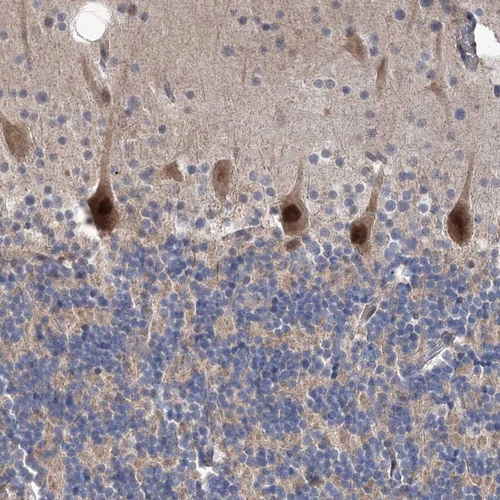

Immunohistochemical staining of human cerebellum shows strong nuclear and cytoplasmic positivity in purkinje cells.